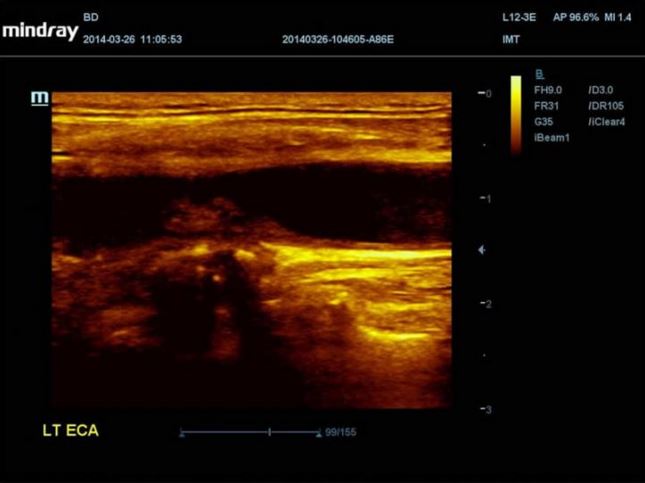

MINDRAY DC-70

Aparat DC-70

Aparat DC-70 daje znacznie więcej. Jego unikalne sterowanie dotykiem i gestem zostało zaprojektowane w taki sposób, by usprawnić płynny obieg czynności. Czystość obrazu uzyskiwana dzięki innowacyjnej technologii głowic w aparacie DC-70 pozwoli wykryć anomalie lub nawet niewielkie zmiany. Narzędzia ułatwiające użytkowanie, obejmujące między innymi wiele pakietów do automatycznych pomiarów pomagają zredukować czas skanowania, standaryzować protokoły badań, zwiększyć produktywność i otoczyć pacjenta jeszcze lepszą opieką.

Zakres aplikacji z pakietami automatycznych pomiarów obejmuje Smart OB, Smart NT, Smart-V, Auto IMT, Auto LV i automatyczny obrys i zliczanie PW,